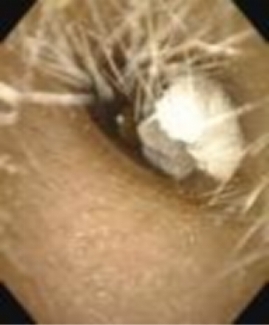

4月11日,来自湖南衡阳的10岁女孩果果,因耳痛、耳闷塞来到湖南省耳儿童医院耳鼻咽喉头颈外科。据家长描述,果果昨日在校时感觉双耳瘙痒,便将草稿纸撕成碎片塞进双耳挠痒,不成想痒痒没止住,纸片却越推越深,因担心被家长责骂不敢声张,还偷偷用水灌进耳道,想让纸泡软后流出来。直至晚上,纸团不但没有流出来,她还出现了耳部疼痛及闷胀感,才不得不向家长吐露实情。接诊医师立即安排患儿进行耳内镜检查,屏幕画面清晰显示,左侧耳道被纸团完全堵塞,右侧耳道被纸团大部分堵塞,异物已遇水膨胀。医护人员立即凭借娴熟的操作技巧将其取出。短短数分钟便顺利取出所有纸团碎片,孩子耳痛、闷胀感迅速缓解。